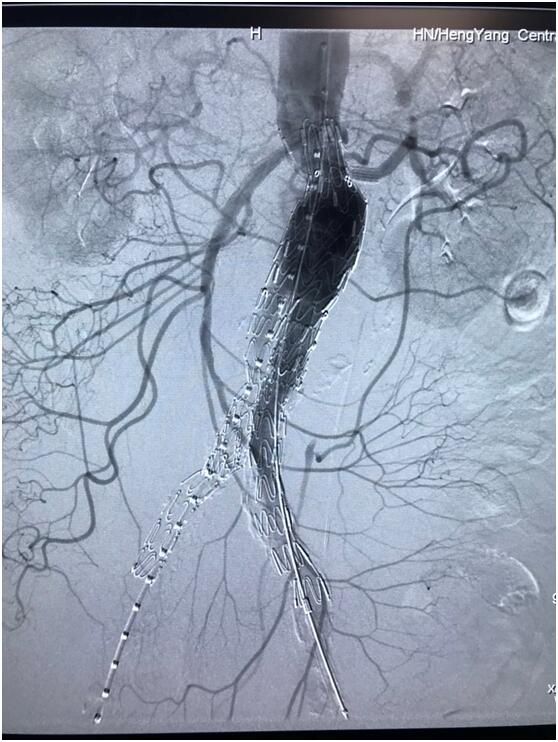

患者因腹部搏動性腫塊行成已有4年,伴右下腹疼痛6小時入院,既往有高血壓病史,患者入院后血壓177/96mmHg,醫(yī)護(hù)人員隨即予以控制血壓、止痛處理,CTA檢查提示患者有腎下腹主動脈瘤,合并心 、肝 、肺 、腎等重要臟器疾患,根據(jù) Laplace定律,動脈瘤直徑越大壓力越大,老人動脈脆弱,動脈瘤隨時有破裂的可能性,其危險性大。血管介入科排除各種困難,在麻醉科協(xié)作下行腹主動脈瘤覆膜支架隔絕術(shù)(“褲衩”支架植入),手術(shù)持續(xù)了1個半小時,患者術(shù)后安返病房,麻醉醒后露出了微笑,向醫(yī)務(wù)人員伸出大拇指。

血管介入科行腹主動脈瘤覆膜支架隔絕術(shù)(“褲衩”支架植入)。圖3